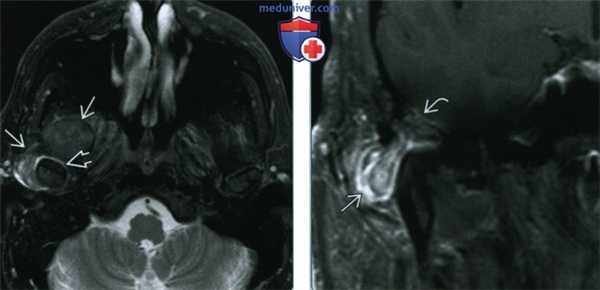

(Справа) Сагиттальная КТ в костном окне у этого же пациента позволяет лучше визуализировать обызвествления и оценить их расположение по отношению к височно-нижнечелюстному суставу. Обратите внимание на деминерализацию и эрозии костных структур, образующих суставную ямку, обусловливающие дефект средней черепной ямки. Нижнее суставное пространство сдавлено, но в остальном сохранно. (Слева) При МРТ Т2ВИ FS в аксиальной проекции у пациента с болезнью депонирования кальция пирофосфата возле правою височно-нижнечелюстного сустава визуализируется патологический участок с неоднородным, преимущественно гипоинтенсивным сигналом. Наблюдается жидкость в суставном пространстве вокруг головки мыщелка нижней челюсти.

(Справа) При МРТ Т1ВИ FS с КУ в корональной проекции снизу и снаружи визуализируется объемное образование, накапливающее контраст. Отмечается дефект кости, формирующей суставную ямку, и легкое контрастное усиление твердой мозговой оболочки; но явные признаки распространения процесса в полость черепа отсутствуют.

(Слева) При МРТ Т2ВИ FS в аксиальной проекции у пациента с болезнью депонирования кальция пирофосфата возле правою височно-нижнечелюстного сустава визуализируется патологический участок с неоднородным, преимущественно гипоинтенсивным сигналом. Наблюдается жидкость в суставном пространстве вокруг головки мыщелка нижней челюсти.